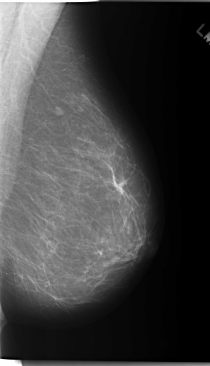

C_0169_1.RIGHT_MLO

C_0169_1.LEFT_MLO

C_0169_1.RIGHT_CC

C_0169_1.LEFT_CC

DATE_OF_STUDY 27 2 1996

PATIENT_AGE 40

DENSITY 2

LESION_TYPE CALCIFICATION TYPE AMORPHOUS DISTRIBUTION CLUSTERED

ASSESSMENT 4

SUBTLETY 2

PATHOLOGY MALIGNANT